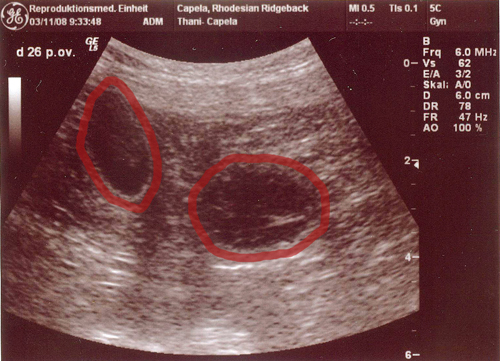

| Es ist heute so weit gewesen. Der große Tag den wir voll Spannung erwartet haben stand vor der Tür: Thani´s Ultraschalltermin in der Reproduktionsmedizinischen Einheit der Ti Ho Hannover. Das professionelle Ärzteteam wird mit Sicherheit ihren Teil dazu beigetragen haben das wir stolz berichten können das Thani tragend ist. Es haben sich zahlreiche Fruchthüllen gezeigt, die schön gleichmäßig in Größe und Abstand aneinander gereiht waren. Wie auch bei ihrer ersten Ultraschalluntersuchung beim A-Wurf war sie auch diesmal recht lebhaft und konnte die Untersuchung nicht ruhig ausharren. Sie stand allerdings auch mit dem Hinterteil zum Ultraschallgerät und versuchte die ganze Zeit neugierig zu gucken was sich da hinter ihrem Rücken abspielte. Auch das ständige Wedeln mit der Rute oder dem Team ein Nasenstüber zu verpassen, brachte etwas Unruhe ins Bild. Dennoch hat es gereicht um von manchen auch die kleinen Herzchen schlagen zu sehen. Ajani und Thani haben ganze arbeit geleistet, sehr schnell und ebenso sehr effektiv. Nun sind wir ganz gespannt was sich uns in ein paar Wochen offenbaren wird….. Eins können wir versprechen, es wird uns eine ereignisreiche Adventszeit bevorstehen. Die Instinktsicherheit dieser beiden RR´s hat uns wieder mal gezeigt das man den Dingen ihren lauf lassen , und man sich nicht zu viele Gedanken machen sollte. Ob nun der Deckakt schnell wie normal üblich über die Bühne geht oder man die Hündin nicht sofort zur Ruhe bettet, hat uns auch dieses mal gezeigt das es mit Sicherheit nicht ausschlaggebend ist. Karolina kann bestätigen das es richtig lustig war Thani danach zu sehen :-) wie ausgelassen und fröhlich sie herumgehopst ist und sich genüsslich vor Ajani auf dem Boden gewälzt hat. Der Bräutigam fand es dann zwar doch etwas merkwürdig als sie gleich angefangen hat Löcher im Garten zu buddeln, aber ich hätte ihr nie diese harmonischen Erlebnisse rauben wollen indem ich sie gleich auf ihren Hundeplatz geschickt hätte. Aber wer Thani kennt weiß das das nicht zu ihr passen würde :-) Nun können wir etwas gelockerter dem großen Tag entgegenschauen und werden unser möglichstes tun Thani optimal zu unterstützen. Unsere Große ist sehr entspannt und befindet sich in bester Kondition. Wie es sich für eine Trächtigkeit gehört glänzt ihr Fell mehr als zuvor und ein kleines Bäuchlein lässt sich bei scharfem Blick auch schon erkennen. Der Appetit ist zwar etwas gezügelt aber das ist ja auch eine weitere Begleiterscheinung zu diesem Zeitpunkt. Wir